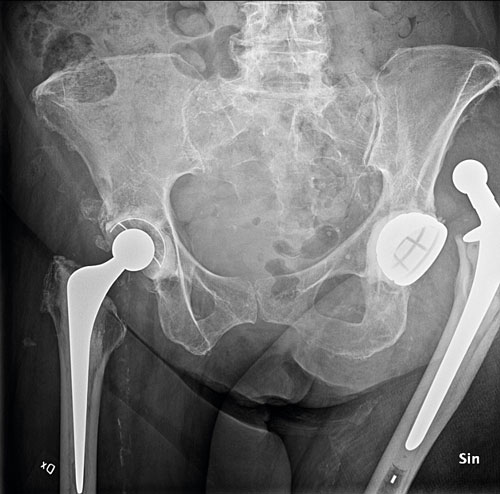

Hel- eller halvprotes. Åldrade multisjuka patienter med låga funktionskrav opereras med halvprotes där man inte ersätter acetabulum (ledpannan). Patienter som har lång förväntad överlevnad, är kognitivt intakta och har god gångförmåga opereras med helprotes [11].

Fördelar med halvprotes är kortare operationstid och mindre kirurgiskt trauma. Nackdelar med halvprotes är bl a kortare protesöverlevnad och risk för revision till helprotes framför allt på grund av slitage i acetabulum. Patienter som opereras med helprotes har bättre funktion i höftleden, mindre smärta och lägre risk för revision. Risken för protesluxation är hög­re vid hel- än halvprotes.

Frakturpatienter opereras med cementerad protes via direkt lateralt snitt (även kallat anterolateralt snitt). Direkt lateralt snitt minskar risken för protes­luxation jämfört med bakre snitt, som vanligen används vid elektiv proteskirurgi. Att förankra protesen med hjälp av bencement minskar risken för peroperativ fraktur, tidig lossning och protesnära fraktur jämfört med cementfri teknik [11, 12].

Patienter som drabbats av höftfraktur har förhöjd risk för ytterligare osteoporosfrakturer. Patienten på bilden hade tidigare opererats på grund av vänstersidig pertrokantär fraktur med märgspik och var nu aktuell med en liknande högersidig fraktur. Patienten hade även färska högersidiga ramusfrakturer.

Pigg och aktiv 77-årig patient med helprotes på grund av artros på höger sida och höftfraktur på vänster sida. Den vänstersidiga protesen hade luxerat ett flertal gånger, och patienten hade genomgått en cup-­revision. Protesen hade dock återigen luxerat. Patienter som är akutopererade med höftproteser på grund av fraktur har högre risk för protesluxation än de som är opererade elektivt, t ex på grund av artros.